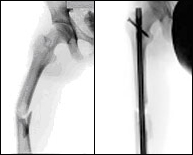

Nos referimos en este apartado a la porción media del fémur, a su diáfisis. Las fracturas en esta localización se asocian frecuentemente a traumatismos de alta energía como accidentes de tráfico o caídas desde grandes alturas y suelen asociarse a fracturas a otros niveles constituyendo lo que denominamos politraumatismo. Se han descrito también fracturas de estrés en atletas de competición después de sobreesfuerzo repetitivo pero son muy poco frecuentes. El tratamiento es eminentemente quirúrgico proponiéndose un tutor intraóseo colocado a través deuna mínima incisión (menos de 3 centímetros) con la finalidad de quitar el dolor, restituir la longitud del muslo e iniciar cuanto antes el movimiento.